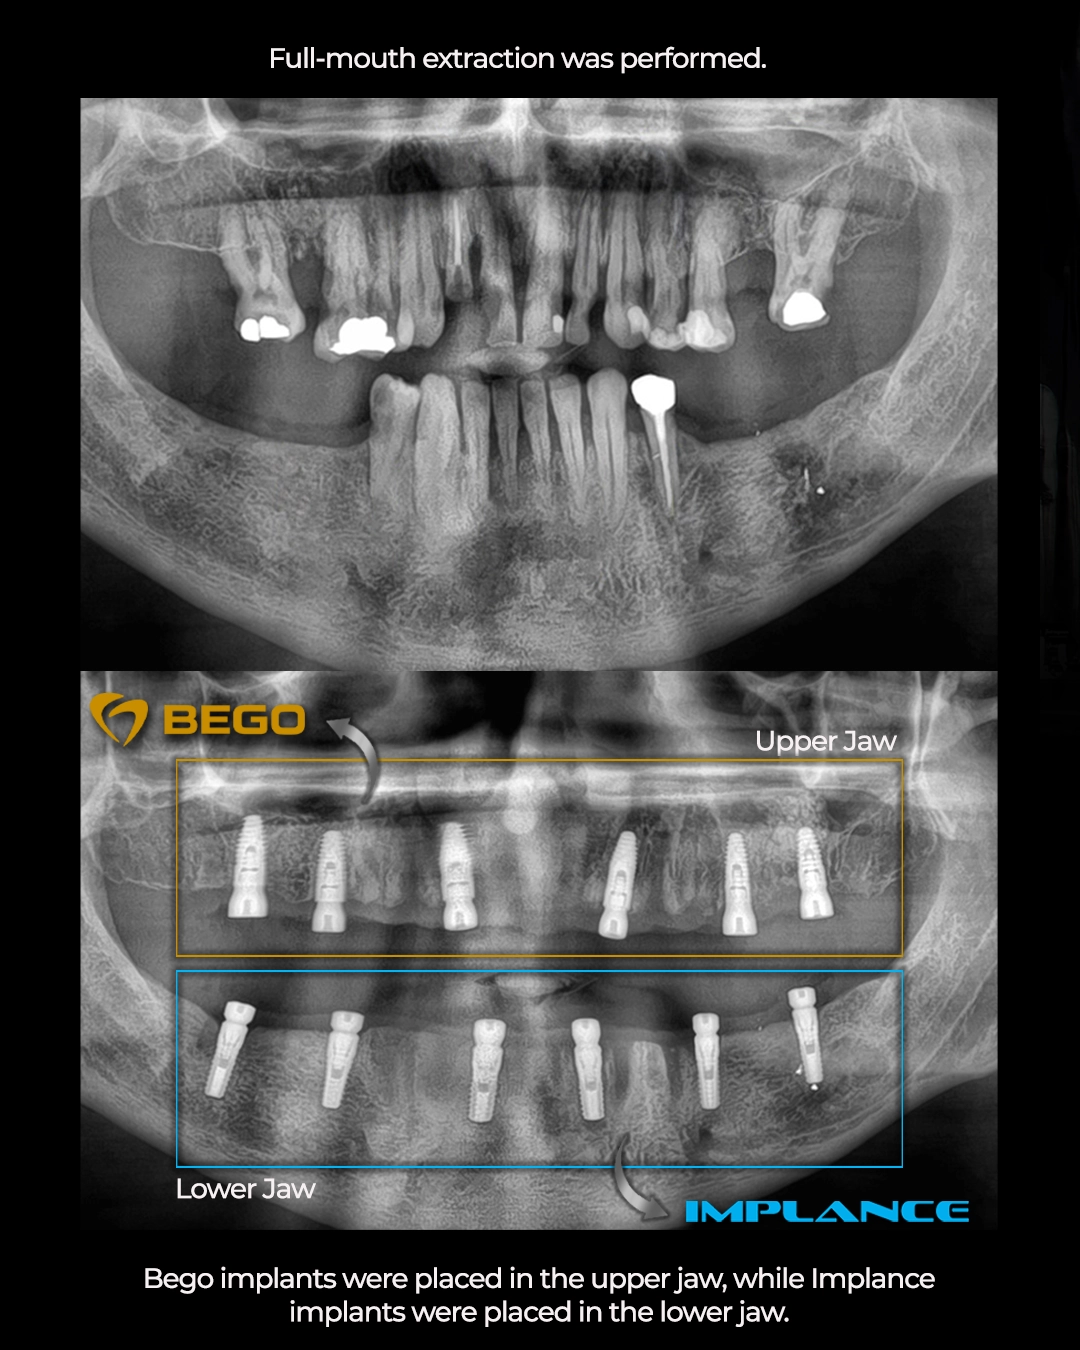

Following extractions, twelve dental implants were strategically positioned, six in the upper jaw and six in the lower jaw. The clinic’s approach to implant selection reveals attention to detail that distinguishes premium care from standard treatment.

Strategic Implant System Selection: BEGO and Implance

For Anes’s upper jaw, the surgical team selected BEGO implants. As detailed in previous case studies, BEGO implants feature the TiPurePlus surface treatment on Grade 4 commercially pure titanium, creating exceptional conditions for rapid osseointegration. The self tapping thread design and integrated platform switching make BEGO implants particularly suitable for the maxillary (upper) arch where bone density tends to be lower and anatomical structures like the maxillary sinus require careful navigation.

For the lower jaw, Implance implants were chosen. The mandible (lower jaw) typically presents denser bone and different biomechanical loading patterns compared to the maxilla. Implance implants offer specific advantages in these conditions, with design characteristics optimized for the mandibular bone density and the higher occlusal forces experienced in the posterior lower arch.

This differentiated implant selection, using different systems for upper and lower jaws, exemplifies International Plus’s evidence based approach. Rather than applying a one size fits all solution, the clinic selects implant systems based on specific anatomical and biomechanical requirements of each jaw.

Upper Jaw Implants: BEGO (6 implants, TiPurePlus surface)

Lower Jaw Implants: Implance (6 implants)